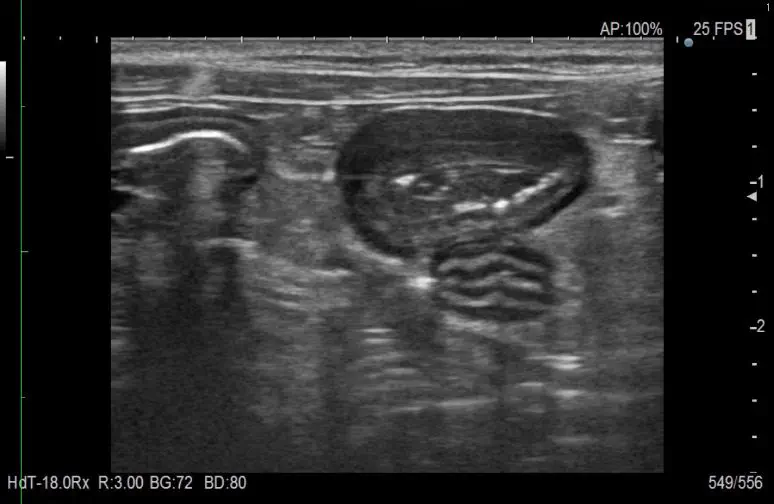

超音波検査(エコー)

超音波検査は身体に無害で痛みがない検査です。お腹の臓器だけでなく、心臓や肺の病変、頸部の甲状腺やリンパ節などあらゆる臓器の観察に活用されます。また、尿や腹水、胸水などの液体採取にも欠かせません。

リンパ腫